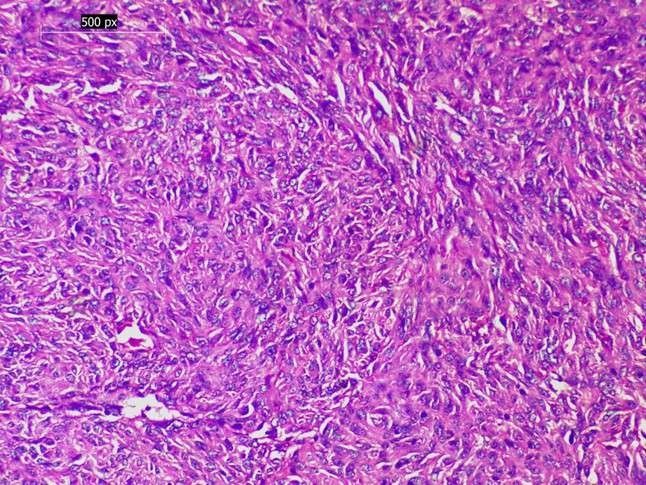

The histological findings were found to be mainly due to inflammatory lesions, which comprised 70 percent of all the biopsies, mostly representing chronic gastritis. Malignant lesions constituted 24% of cases, the most common type of which was gastric adenocarcinoma, and then the squamous cell carcinoma of the oesophagus. Benign neoplasms were isolated to gastric polyps (4.5%), and the premalignant changes were rare (1.5%), including intestinal metaplasia, dysplasia, and Barrett's oesophagus with dysplasia (see Table 2, Figures 1 and 2).

The most common cases of chronic gastritis were found in patients who presented with abdominal pain and dyspepsia, and related in many cases to biopsies that were taken in the pylorus. A strong relationship was shown between malignant lesions and older age; the lesions were observed in patients over 40 years old and with a strongest male predominance in the population 3: 1). Ulcer proliferative growths had nearly a perfect correlation with malignant histology by endoscopy, whereas antral/perinatal gastritis was associated with inflammatory lesions (see Table 3, Figures 3-5).

Figure 5. Gastrointestinal stromal tumor (GIST). Proliferation of spindle-shaped cells arranged in fascicles, consistent with GIST (H&E, 200×)